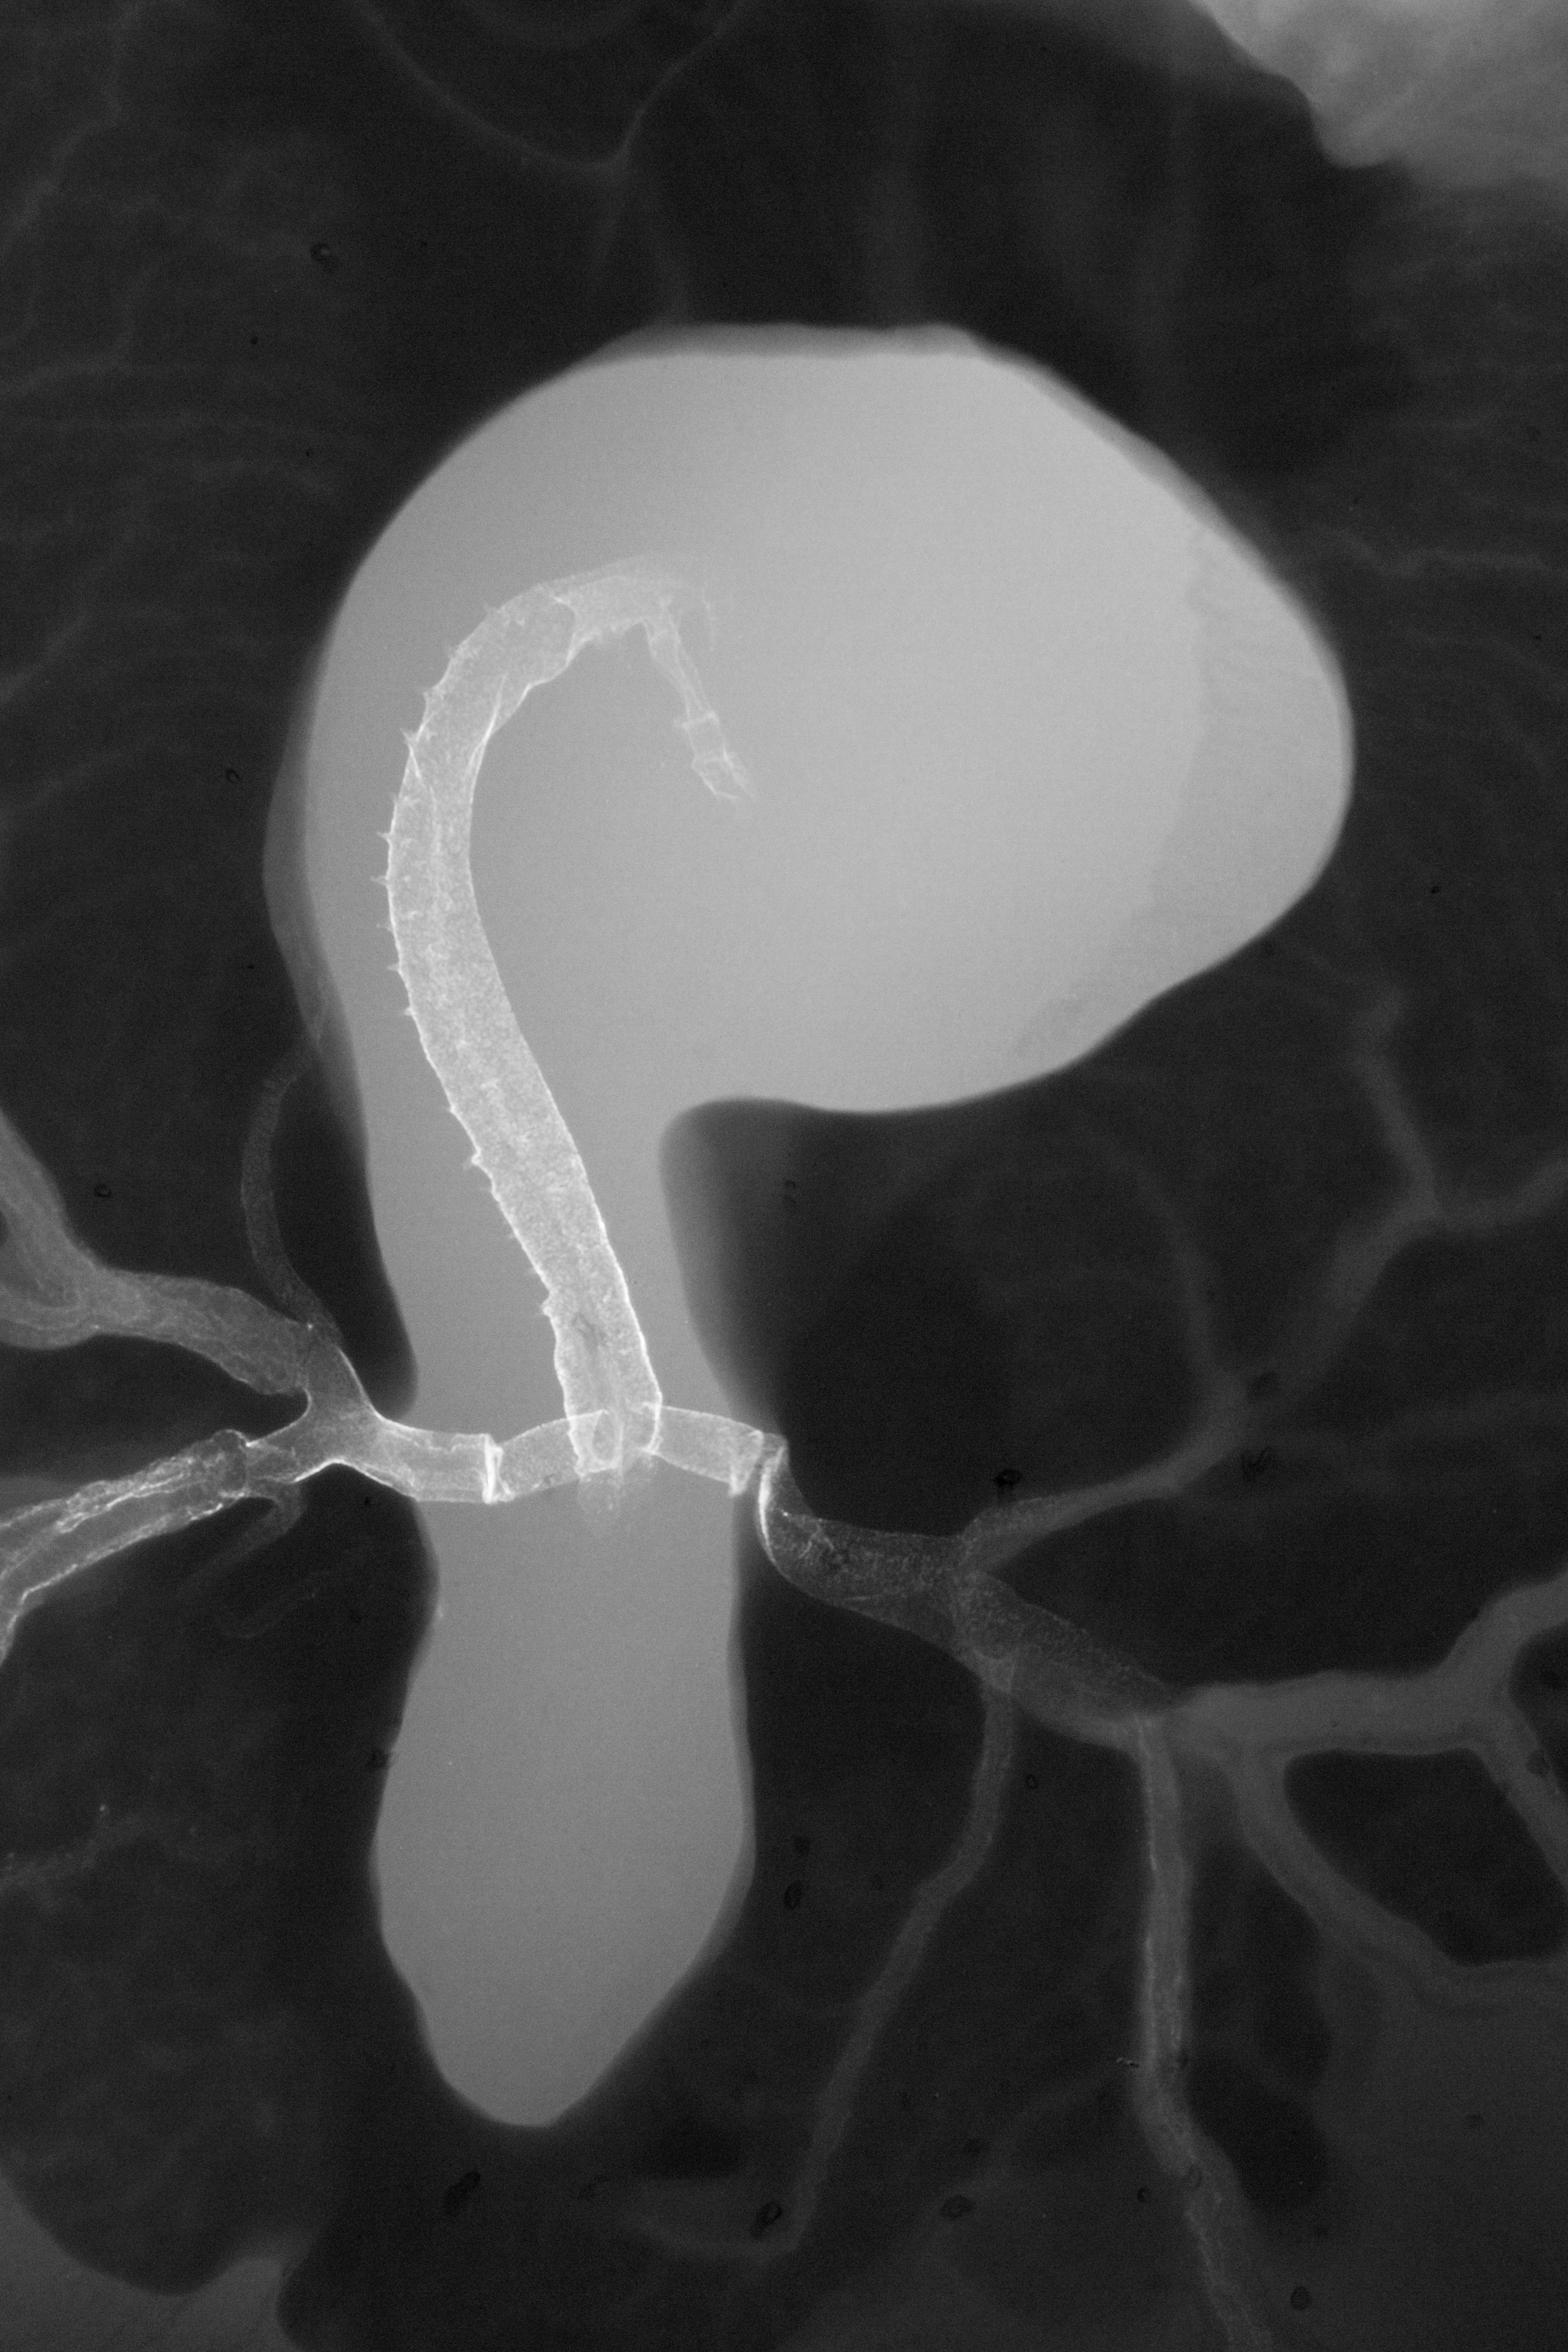

Chick Embryo Microangiography

Hamburger-Hamilton (HH) Stage 16 (approx. 2.1 - 2.5 days)

X-Ray Micrographs